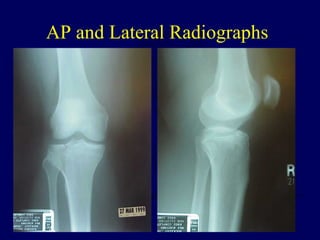

AP and Lateral Radiographs